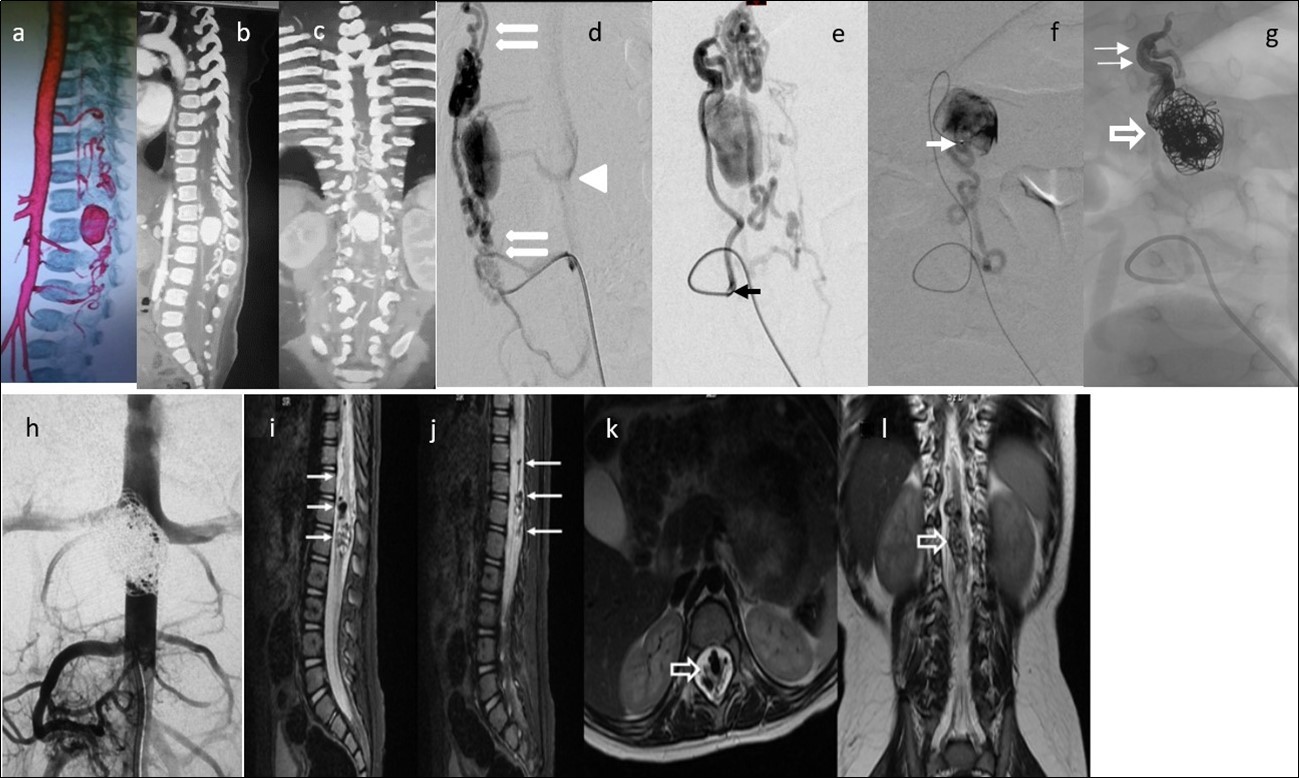

Figure 4.Case 4: a) 3D CTA shows a gigantic venous pseudoaneurysm occupying the spinal canal at the T12-L1 vertebral levels with tortuous veins above and below the lesion. b) and c) 2D reformatted images. d) and e) Selective right L3 angiogram through a 4F guiding catheter (arrow) in lateral and AP projections showing an enlarged PSA feeding a huge venous varix with ascending and descending perimedullary veins (thin arrows) and with segmental epidural draining veins at the fistula level (arrowhead).f) A microcatheter was navigated up to pseudoaneurysm (arrow) g) In the venous sac, 21 GDC coils were deployed (open arrow) and the microcatheter tip was pulled back to the fistulous site followed by Onyx 18 injection to fill up the foot of the ascending draining vein (thin arrows). h) Post-embolization abdominal aortogram (late phase) failed to demonstrate any remaining shunt. i) to l) Multiplanar T2 MR images 6 months’ post-embolization showing absence of flow, and artifacts due to coils and Onyx (arrows). No spinal cord hyperintensity was observed. Patient starting to walk independently with minimal right foot dorsiflexion paresis. He gained complete sphincter control.

Two out of 4 patients were diagnosed and studied preoperatively with both spinal MRI and CT scans, 1 patient with MRI and the other patient with CT/CT Angiography with 3D reconstruction. Large and tortuous flow voids with large to giant venous pouches or pseudoaneurysms (3 of our cases - type c) causing compression of the spinal cord were found lying ventrally and, in another one, posterolaterally to the spinal cord. Hyperintensity in T2W sequences in the spinal cord was noted in all of them. There were no cases where a hemorrhage was exhibited. The angiographic studies confirmed the 4 large or giant pouches at the draining vein fed by ASA and or PSA and ascending (2 cases), descending (1 case) or metameric (1 case) venous drainage. The blood flow was moderate in 1 case and very fast in the other 3 patients (see Table 2 and Figure 1, Figure 2, Figure 3, Figure 4).

We used transarterial approach and a single session achieving complete obliteration of the fistulae while preserving the normal vasculature, mainly the ASA, in all of our 4 cases using either different concentrations of n-bca alone tailored to the blood flow velocity (cases 1,2 and 3), or a combination of coils and onyx 18 (case 4). In this last case, the high flow fistula and the presence of a giant pseudoaneurysm at the venous varix compressing the spinal cord prompted us to deploy coils in the sac and in the draining vein to slow down the blood flow and decrease the chance of distal embolism. To date, we do not have Onyx of higher concentration than Onyx18 available in our country. In high flow macrofistulae, our strategy to slow down the flow to allow casting of the polymerizing embolic mixture in the fistulous site avoiding distal embolism includes lowering mean arterial pressure down to 60-70 mm Hg pharmacologically, by embolizing with concentrations of 66% of n-bca in lipiodol, as well as the placement of detachable coils in the event of very high flow with pseudoaneurysms at or very close to the fistulous site as a first step, to trap the liquid embolic material injected as second step (see Figure 1, Figure 2, Figure 3, Figure 4).